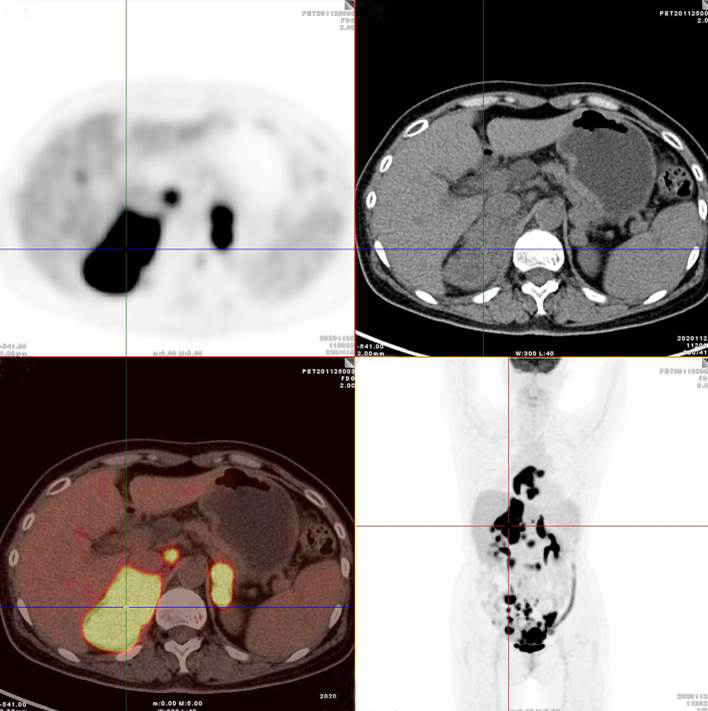

胃、雙腎上腺病灶、腹膜后淋巴結(jié)放射性攝取明顯增高

腸系膜多發(fā)淋巴結(jié)放射性攝取增高

多段小腸腸管放射性攝取增高